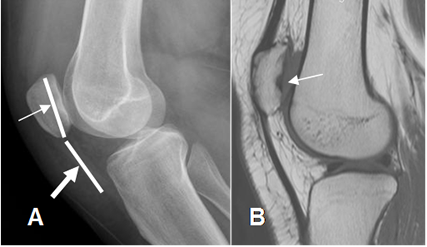

Fig 161. Inestabilidad patelar vertical.

A: Rx lateral. Patela alta. La longitud de la patela (Flecha delgada), es menor que el espacio entre su polo inferior y el sitio de inserción. (Flecha gruesa).

B: RM sagital en T1. Patela alta, sin alteración del mecanismo extensor. Existe lesión osteocondral, en la parte posterior.